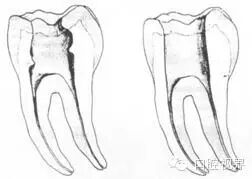

左图为正常开髓孔的大小和位置。左边图为下颚,右边图为上颚。